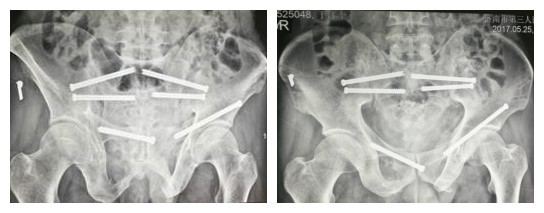

患者于伤后第 6 天病情稳定后,在气管插管全麻下行机器人辅助骨盆骨折经皮空心螺钉内固定术。按机器人操作流程,采集图像,规划路径,前环分别在左右耻骨上支各置入空心螺钉 1 枚固定,后环分别于骶骨左右各置入骶 1、骶 2 空心螺钉 2 枚。所有置钉均一次成功,手术时间 150 min,手术切口 6 个,平均 2 cm,出血 20 ml。患者复苏后无神经损伤症状,第 2 天进行功能锻炼,床上练习双下肢髋、膝关节主动或被动屈伸运动。伤口一期愈合,术后拍片骨折对位良好(见图 3-5)。CT 平扫示螺钉置入位置满意,均未穿出骨皮质。术后 5 周可持双拐下地行走,8 周开始保护性部分负重活动,于 12 周完全负重行走。术后随访 12 个月,3 个月内骨折愈合,无复位丢失。

图 1、2 术前 CT 扫描三维重建示双侧耻骨上、下支及双侧骶骨骨折。